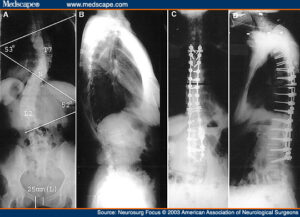

Per effettuare l’analisi è sufficiente un semplice prelievo di saliva del paziente: dopo due settimane l’azienda rende disponibile al medico curante un report con un punteggio indicante la probabilità del paziente di andare incontro ad un peggioramento della scoliosi. Per esempio, nel caso risulti il rischio di sviluppare una curvatura della spina dorsale di 50 gradi o più, può essere da subito prescritto un corsetto ortopedico, o addirittura un gesso. ScoliScore è attualmente indicato per adolescenti con scoliosi idiopatica, ovvero a eziologia ignota.